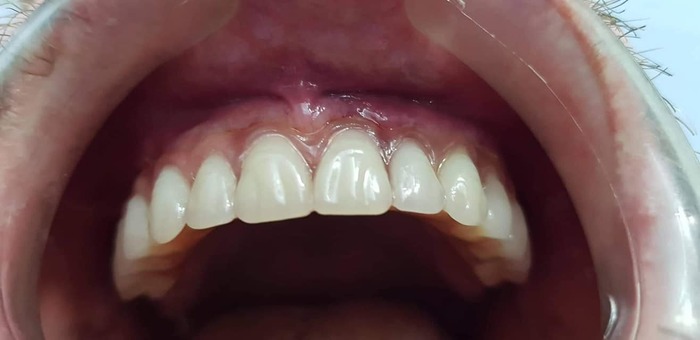

А это - мои новые зубы:

Буду учиться по новой улыбаться, есть и разговаривать - с кем из родственников говорил - отмечают, что с шипящими у меня некоторые проблемы еще есть; но, думаю, с разговорной практикой все наладится.